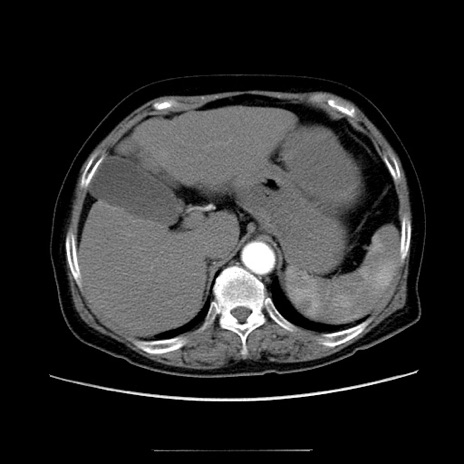

症例5(横断像)

【症例】70歳代女性

【主訴】お腹が張る

【現病歴】1週間くらい前から腹部膨満の自覚あり。昨日夜から増悪したため、本日救急外来受診。

【身体所見】意識清明、BT 36.5℃、BP 165/106mmHg、HR 80bpm、SpO2 98%、腹部:膨満、軟、自発痛・圧痛なし、触診にて不快感あり、腸蠕動音:減弱

【データ】WBC 12600、CRP 1.04